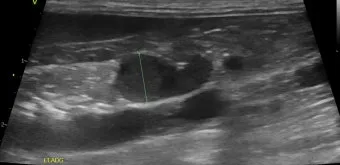

복부 초음파 검사 - 가장 기본적이면서도 중요한 1차 검사예요. 췌장의 크기나 모양 변화, 주변 장기와의 관계를 실시간으로 관찰할 수 있어요. 비용은 보통 15만원-25만원 정도이고, 검사 시간은 20-30분 정도 걸립니다.